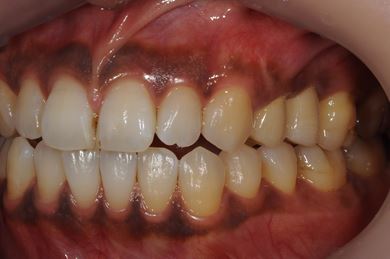

インプラントの症例写真 IMPLANT

| 治療内容 | インプラント2本(ソケットリフト、抜歯即日スピードインプラント)、メタルボンドセラミッククラウン3本(メタルボンドセラミック用土台1本)、ハイブリッドセラミックインレー4本 | ||||||||||||||||||||||||||||||||

| 治療期間 | 10ヶ月 |

治療前